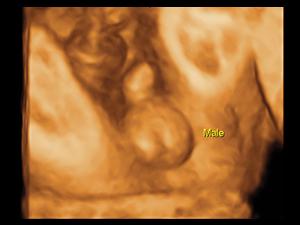

對例行結構性超聲波而言,二維(2D)超聲波已經足夠。三維(3D)及四維(4D)超聲波可說是錦上添花,有助加強孕婦及家人與小生命之間的連繫;大部份孕婦都樂於觀看胎兒3D/4D圖像。倘若經2D超聲波診斷出或懷 疑胎兒結構異常,3D或4D技術有助釐清及確定2D超聲波之診斷,有助孕婦及家人了解異常結構的情況。

懷孕二十八週男性胎兒性器官的三維圖像